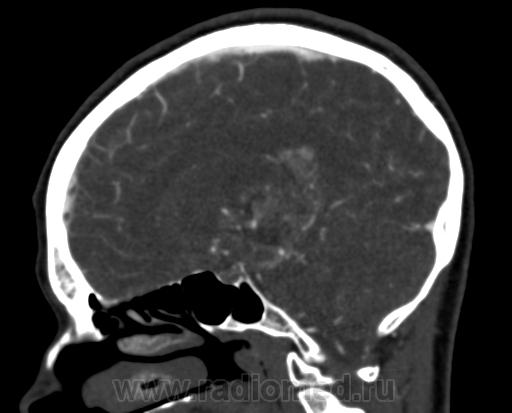

Молодая женщина, 29 лет. Обратилась на прием к неврологу 26.10.12г с  болями в шее, назначено лечение амбулаторно по сосудистой головной боли, остеохондрозу.. После 14.11.12г обратилась к другому неврологу повторно, 16.11.12г направлена в стационар. Жалобы: на снижение зрения, головные боли, головокружения, слабость, повышение температуры. Провели СКТ головного мозга натив и контрастирование. Подскажите пожалуйста, коллеги- Это опухоль? тогда какая (глиобластома, невринома, менингиома?) и локализацию. Спасибо.

Сканы с контрастированием.

Нативное исследование.

Одно можно сказать точно: это не менингиома и не невринома (у тех структура однородная). Это Вам в помощь http://www.radiologyassistant.nl/en/p47f86aa182b3a/brain-tumor-systematic-approach.html

Мне кажется, что тут субэпендимарная глиома. Указываете степень дислокации, накопления и к нейрохирургам.

Согласна с Андреем Юрьевичем. Все остальное возможно, в том числе олигодендроглиома. Впрочем не принципиально. К нейрохирургам!

Только что узнала результаты вскрытия.Гистология пока не готова.

Глиобластома с прорастанием стенки правого бокового желудочка, выраженный отек, смещение срединных структур, вклинение миндалин мозжечка в БЗО.